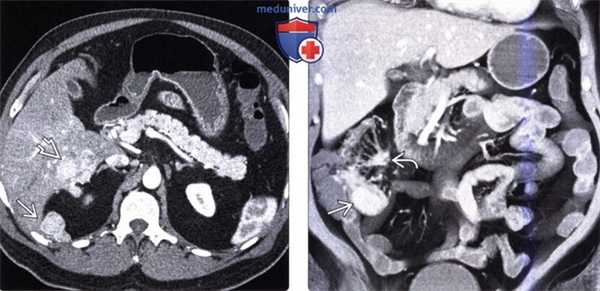

(Слева) На аксиальной КТ у мужчины 54 лет со схваткообразной болью в животе и приливами визуализируются гиперваскулярные метастазы в печени и по брюшине.

(Справа) На корональной КТ у этого же пациента визуализируется гиперваскулярное образование в терминальных отделах подвздошной кишки (первичная опухоль) в сочетании с метастазами в брыжейку с наличием десмопластических изменений в брыжейке подвздошной кишки. Эти клинические и лучевые признаки являются классическими изменениями при карциноидном синдроме.